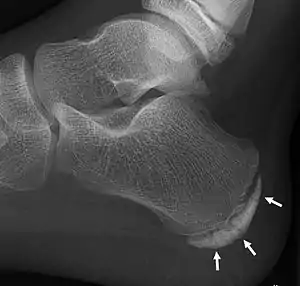

| X-ray of the foot of an 11-year-old child, showing sclerosis and fragmentation of the calcaneal apophysis. This is a sign of low sensitivity and specificity of Sever's disease, because those with Sever's disease may not have it, and this appearance is also present in feet without pain.[1] | |

Children with calcaneal apophysitis commonly complain of pain at the back of the heel. This pain increases with jumping and some running sports. Sometimes, the pain makes children limp and may result in poor sports performance or them not wanting to participate in some sports. The back of the heel is never swollen or red, unless there has been shoe rubbing. When the back of the heel is squeezed from the inside and outside, children with calcaneal apophysitis will report pain. Foot radiographs are not needed to diagnose calcaneal apophysitis as the growth plate can look similar with or without pain. Health professionals should only refer for imaging when the symptoms don't match with the usual presentation or there has been an injury that has resulted in heel pain. Therefore, the diagnosis of Sever's disease is primarily from history and physical assessment.[2]